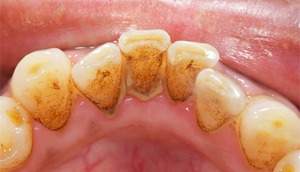

スケーリング

治療前

治療後

| 年齢 | 49歳・男性 |

| 主訴 | 歯石を取りたい |

| 治療内容 | 全顎歯石除去 |

| 治療期間 | 60分 |

| 費用 | 約2,000円(保険適用) (2023年5月現在) |

| リスク・副作用 |

・歯ぐきの炎症が強いと歯石を取る際に出血することがあります。 ・処置後に歯がしみることがあります。 ・歯と歯の間に隙間ができるので、息が漏れ発音しにくいと感じることがあります。 ・歯ぐきの炎症が軽減すると歯ぐきが引き締まり、歯が長く見えることがあります。 |

| 治療方針 | 久しぶりの歯科医院で歯石が硬く多量でした。歯ブラシ指導も併せて行いました。 歯ぐきの中の見えない部分にも歯石が多量に付着しているので今後は縁下歯石除去(SRP)を行なっていく予定です。 |

| 担当者所見 | 歯石がなくなり歯ぐきが改善するとことにより、しみやすいことをお伝えしました。セルフケア指導としては1本ずつ丁寧に磨くことをお話しさせて頂きました。 柔らかめの歯ブラシで斜め45度に歯と歯ぐきの境目に当て磨くこと、洗口剤の使用を提案しました。 |